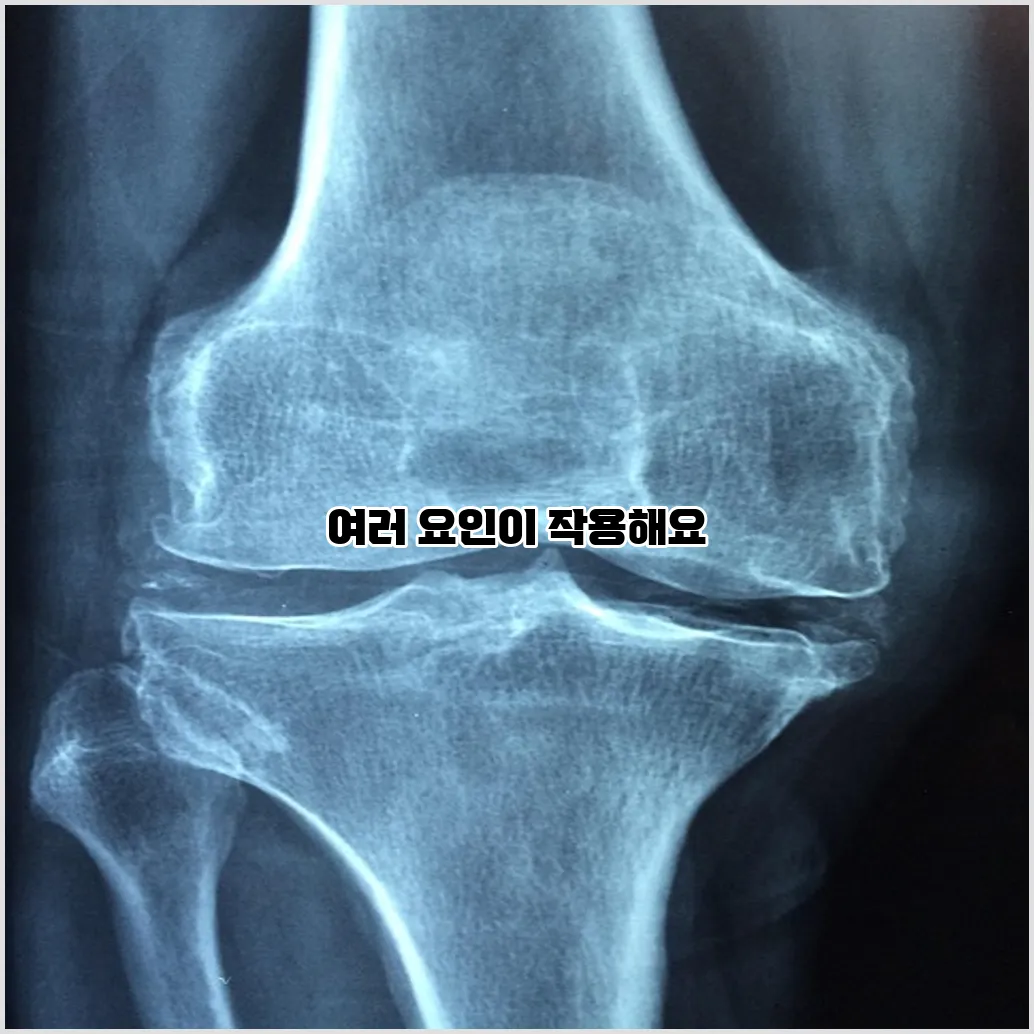

골다공증은 뼈 밀도가 감소하고 뼈 조직이 약해져서 발생하는 질환입니다. 이로 인해 뼈가 쉽게 부러질 수 있으며, 특히 노년층에서 많이 발생합니다. 사람들은 종종 골다공증이 나이 듦의 자연스러운 과정이라고 생각하지만, 이는 예방하고 관리할 수 있는 질환입니다.

골다공증의 주요 원인은 여러 가지가 있으며, 그 중 일부는 유전적 요인이나 생활 습관에서 비롯됩니다. 골다공증 원인으로는 가장 먼저 나이가 들면서 호르몬 변화가 일어나는 것입니다. 특히 여성의 경우 폐경 후 에스트로겐 수치가 감소하면서 뼈의 소실이 급격히 증가합니다.

골다공증의 위험 요인

골다공증의 위험 요인은 여러 가지가 있으며, 이를 이해하는 것이 예방의 첫걸음입니다. 우선 여성의 경우 남성보다 골다공증에 걸릴 확률이 높습니다. 특히 폐경 이후에는 급격히 뼈의 소실이 일어납니다.